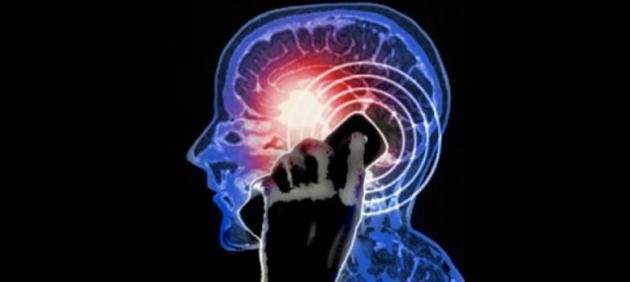

Una delle domande molto discusse e che ancora non ha una risposta chiare e definita è: le onde elettromagnetiche emesse dai telefoni cellulari creano problemi per la salute dell’uomo?

Ad oggi non c’è uno studio che risolve la questione, ma una recente analisi condotta in Australia suggerisce che i telefoni cellulari sono ‘sicuri’ e soprattutto non si possono ritenere una causa di malattie come il cancro o tumore al cervello.

Questo ed altri studi dicono che le onde elettromagnetiche emesse dai telefoni cellulari non provocano gravi stati di salute nell’uomo come è per esempio il cancro, ma questo non toglie che altrettanti studi dicono il contrario. La cosa sicura è che, anche se gli smartphone gravano sulla nostra salute, chi al giorno d’oggi sarebbe disposto a stare senza telefono? La società sarebbe pronta per smettere di usare il telefono cellulare se uscisse uno studio che, con prove incontrovertibili, spiegasse che le radiazioni dello smartphone fanno male?